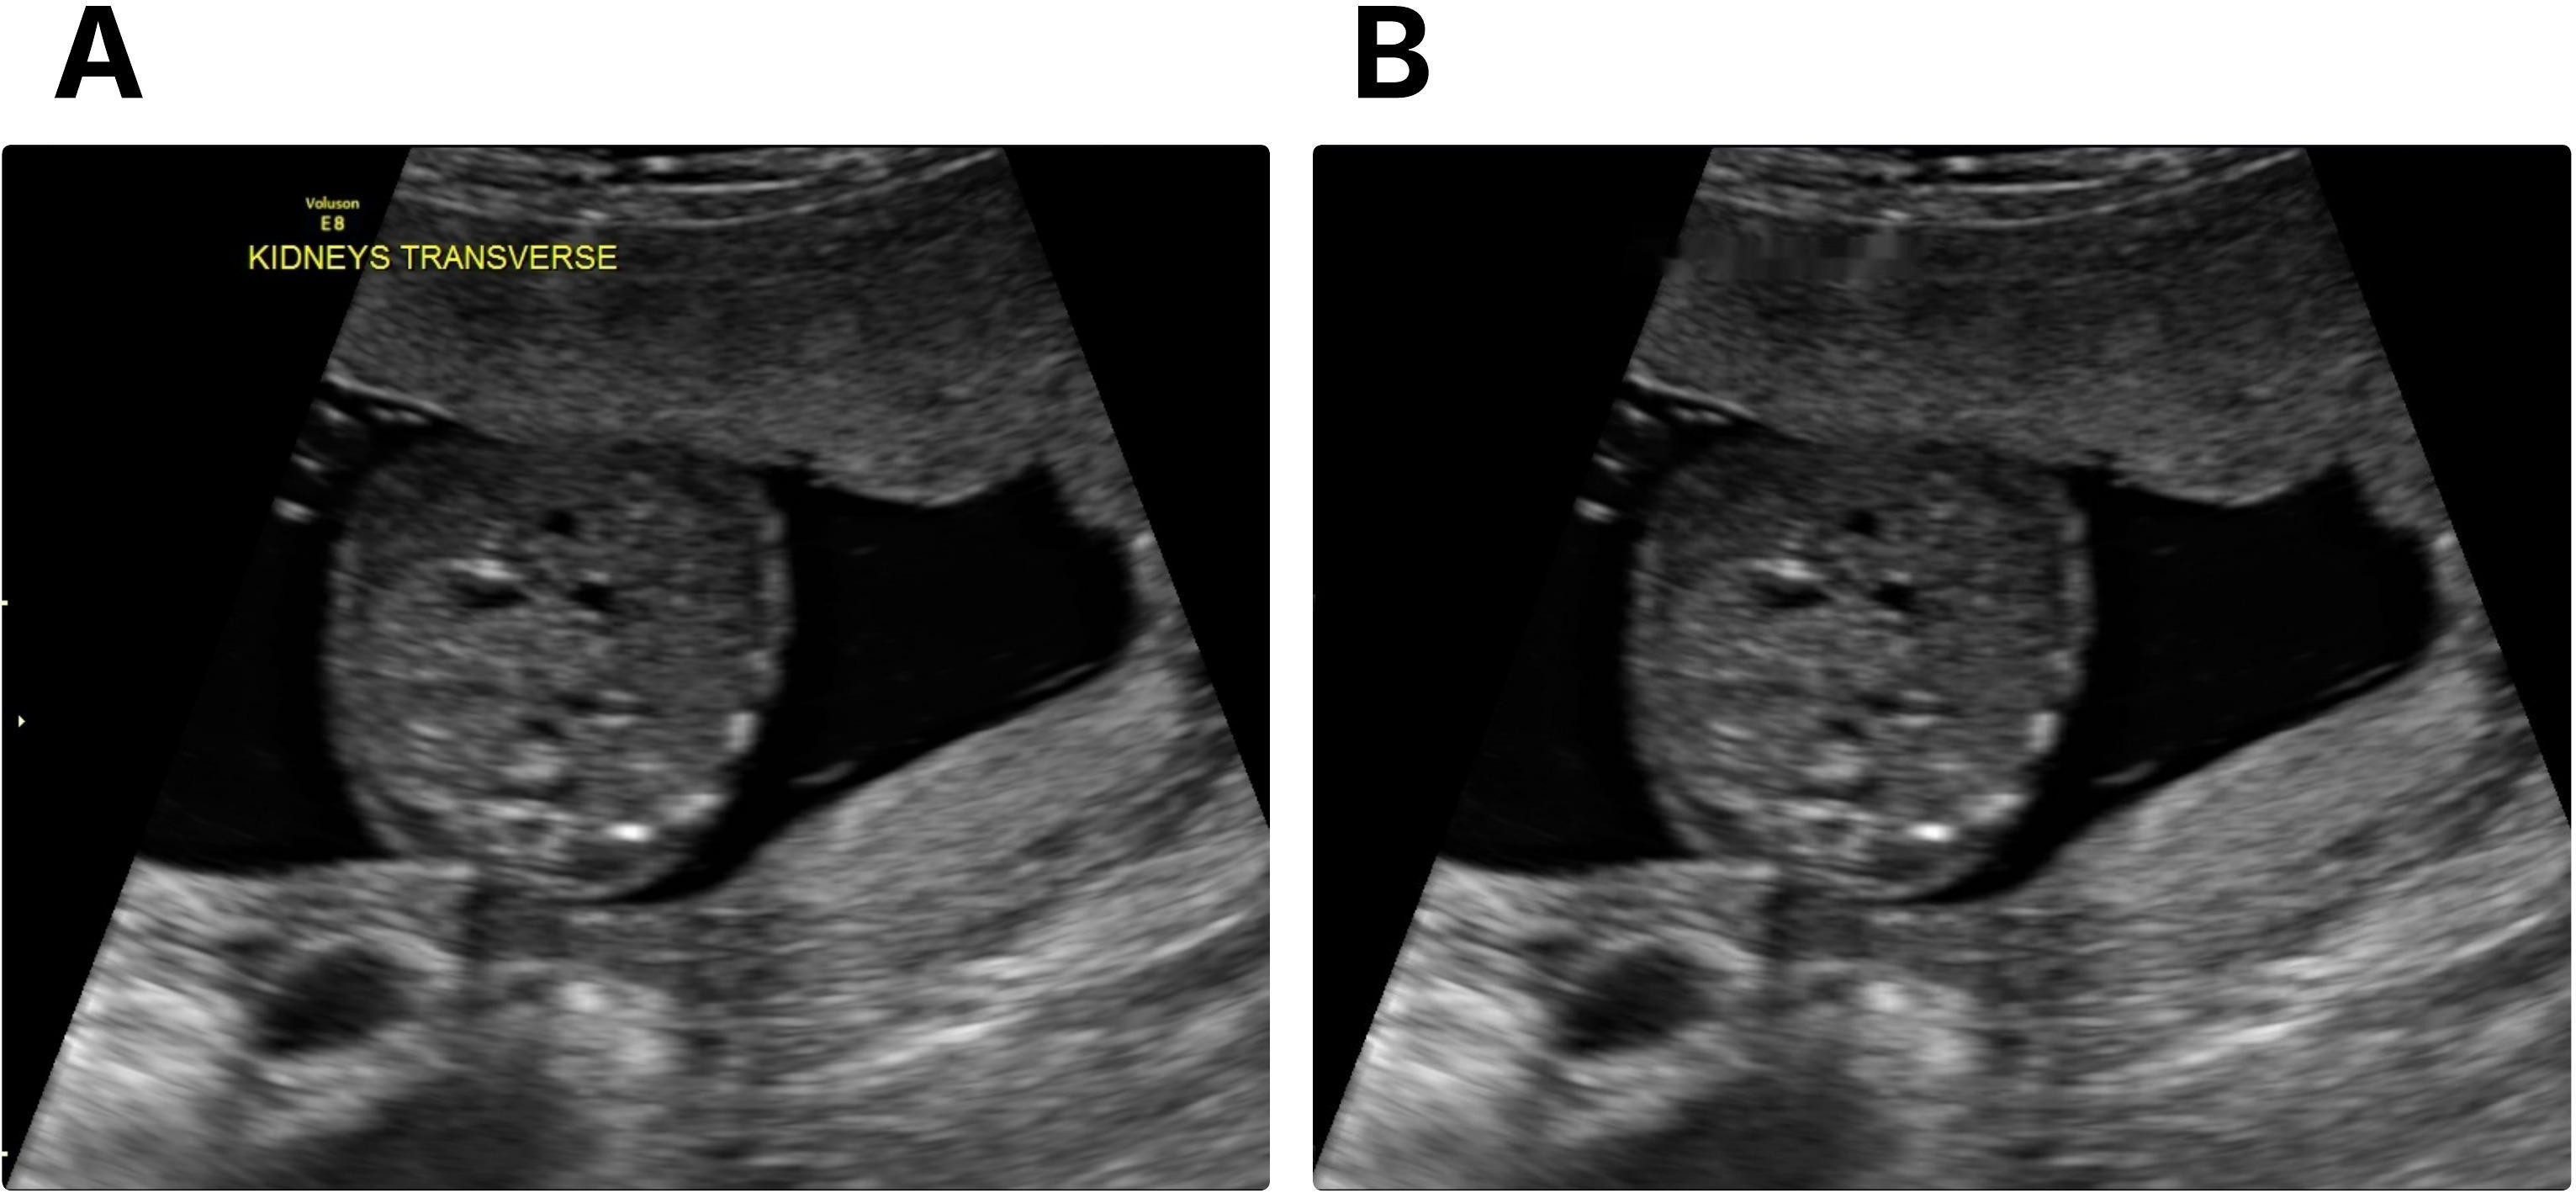

Refer to caption

Figure 1: Prenatal ultrasound examples of renal development. (A) Normal fetal kidney with typical structure. (B) Multicystic dysplastic kidney (MCDK) showing multiple noncommunicating cystic spaces. (C) Urinary tract dilation (UTD) featuring enlarged renal pelvis and collecting system.

All images consisted of two-dimensional transverse abdominal planes, with measurement of the anteroposterior diameter of the renal pelvis. These images were retrieved from the institutional Picture Archiving and Communication System (PACS) and stored in Digital Imaging and Communications in Medicine (DICOM) format. Because the study focuses on a curated set of transverse fetal kidney images, the dataset was assembled to include normal kidneys and two CAKUT phenotypes that can be reliably identified in this specific plane: multicystic dysplastic kidney (MCDK) and urinary tract dilation (UTD) (Fig. 1 shows an example of each class). The combination of MCDK and UTD in the "Abnormal" meta-category is used to apply hierarchical categorization, converting the ML problem into a binary classification task (Fig. 4). UTD cases followed the 2014 classification criteria [13], which set a renal pelvis diameter of 4 mm or greater as the diagnostic threshold. To ensure comparability with abnormal cases, normal samples were selected so that their acquisition years matched those of UTD and MCDK examinations. This produced a balanced and temporally aligned cohort of normal scans. The final normal class consisted of axial kidney images from pregnancies without CAKUT, resulting in an overall dataset ratio of about two normal cases for every abnormal case. Multiple examinations from the same patient were included when available within the gestational age window.